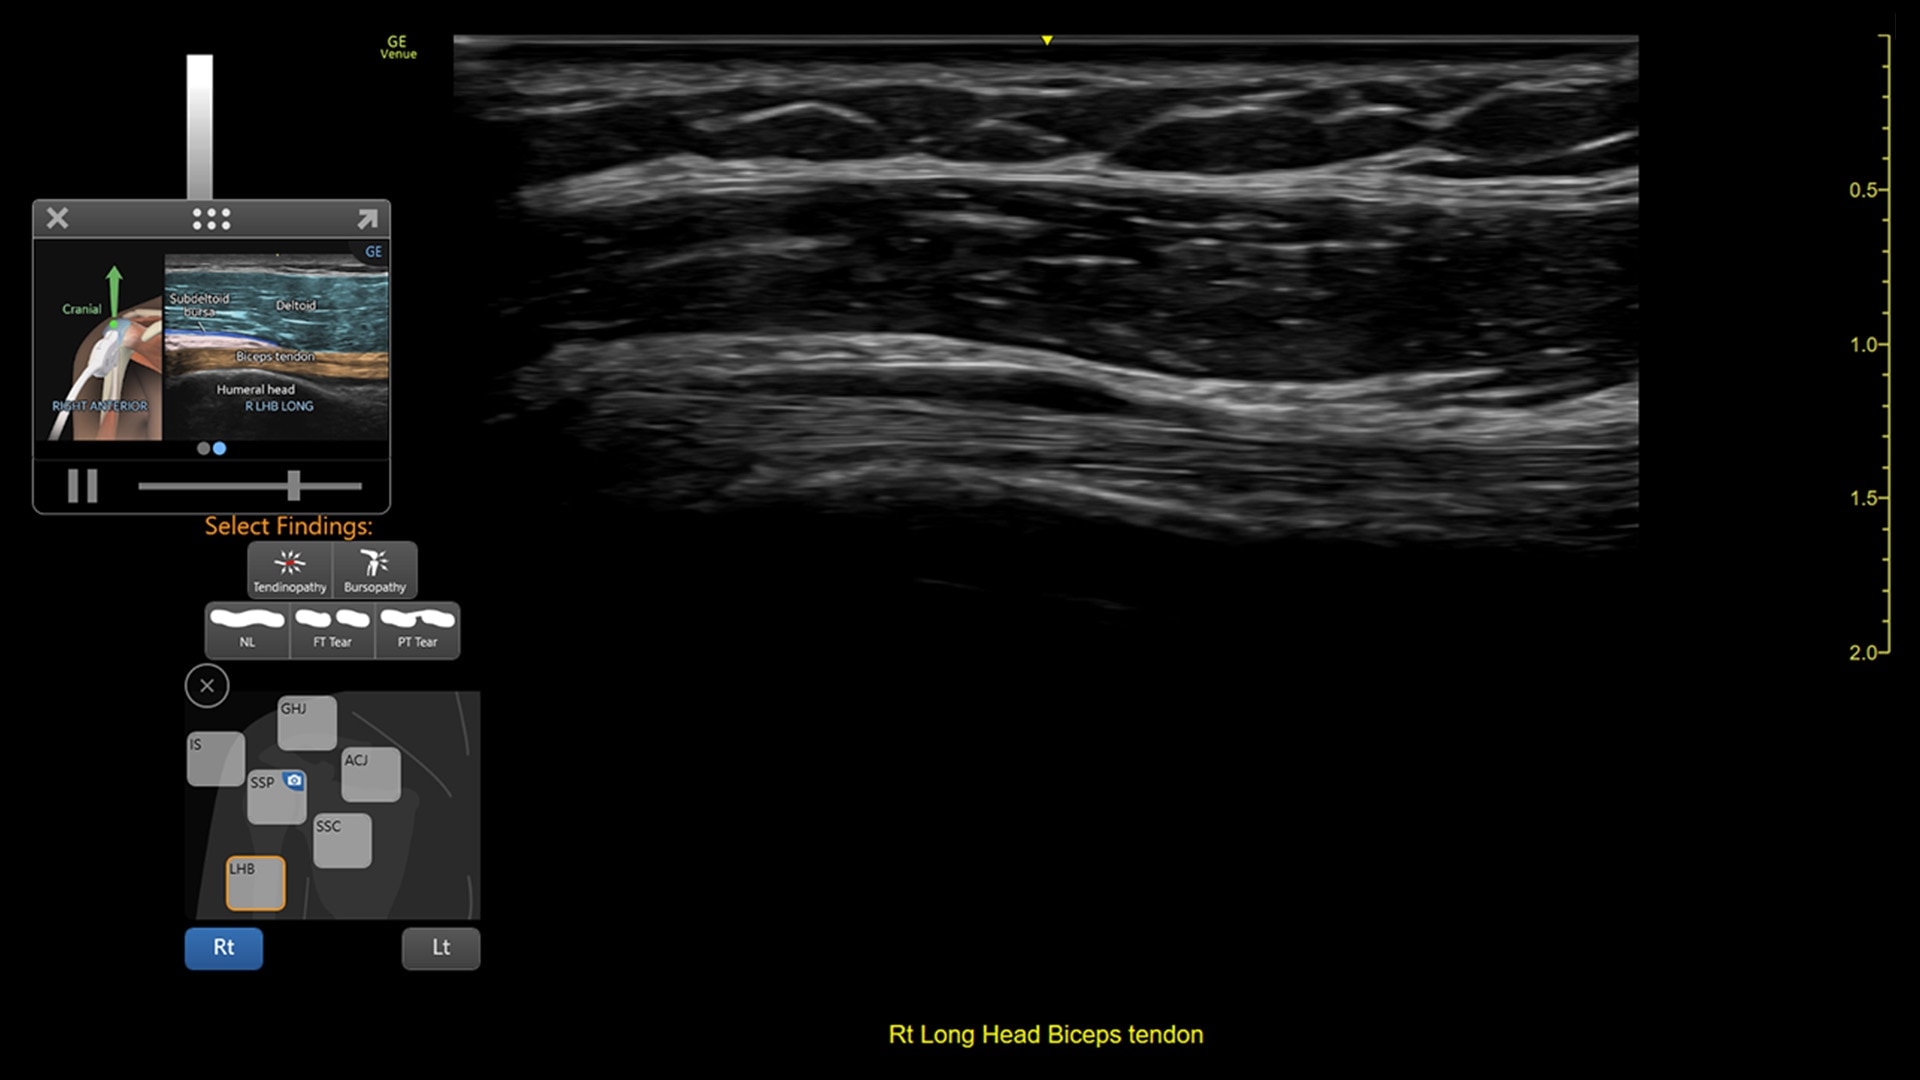

Venue coach MSK

Simplifying MSK scans

This easy-to-use exam documentation tool assists users through exams by providing reference images and anatomy markups. Multiple anatomical areas and helpful video tutorials help clinicians to acquire the scans they need.

MSK Diagrams: Simplifies documentation and assists the clinician in follow up for patients. No need to manually type findings—you can simply assign a label from a pre-populated list that correlates with the images. Get a single view diagram with one click image storing, keep track of assessments and show trends in response to therapy.

Reference Image: Reference image provides anatomy mark-ups to assist novice users in scanning the correct anatomy

Bilateral mode: Helps you to view the opposite side of the same zone for comparison (available for Shoulder preset)